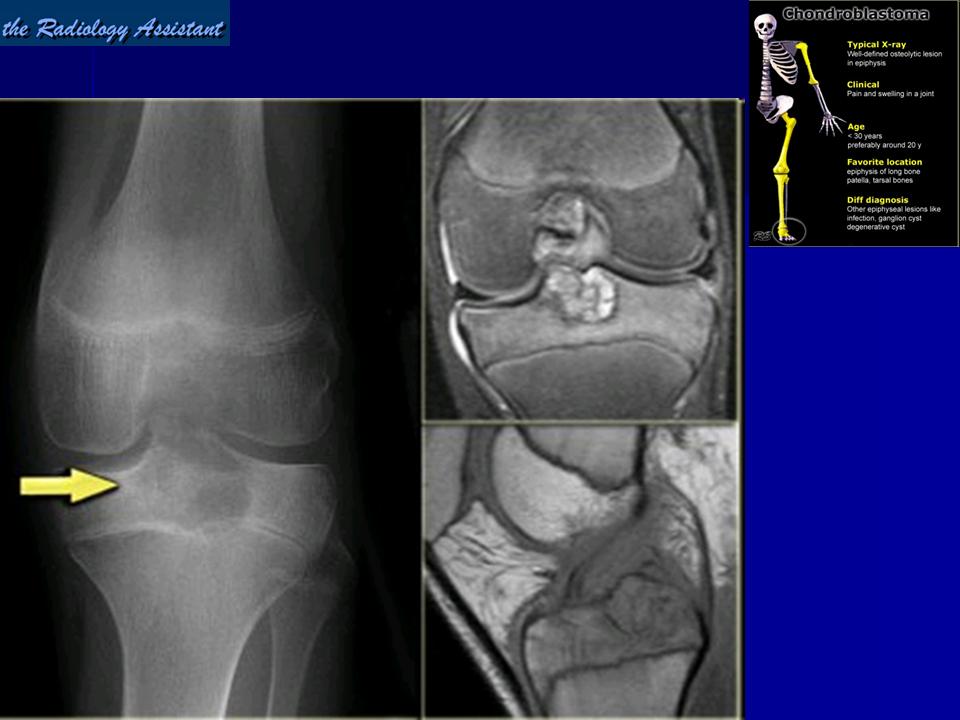

Рентгенологически хондробластома представляет собой сравнительно большой (2-4 см) очаг округлой формы, четко отграниченный от окружающей кости склеротической каймой. На фоне очага в большинстве случаев, но не обязательно определяются плотные включения, напоминающие хлопья ваты.

Хондробластома (кальцифицирующаяся гигантоклеточная опухоль, эпифизарная хондроматозная гигантоклеточная опухоль) - доброкачественная, хрящевая опухоль, развивающаяся в эпифизарных отделах костей. В настоящем исследовании хондробластома выявлена у 5 мужчин и 3 женщин.

Рентгенологическая картина. Хондробластома выглядит как небольшой, от 3 до 6 см литический очаг, центрально или эксцентрично расположенный, с четкими контурами, занимающий около половины площади эпифизарной зоны. Хондробластома плоских костей и мелких трубчатых костей больших размеров, может сопровождаться припухлостью мягких тканей, вздутием кости и периостальной реакцией. Распространение процесса на метафизарную зону встречается часто.